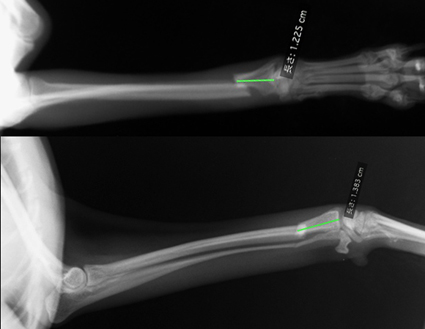

写真(下): 手術後の患部の様子。

創外固定ピンは、白いエポキシ樹脂で固定されています。この上から、ガーゼと特殊包帯によるカバーをかけます。